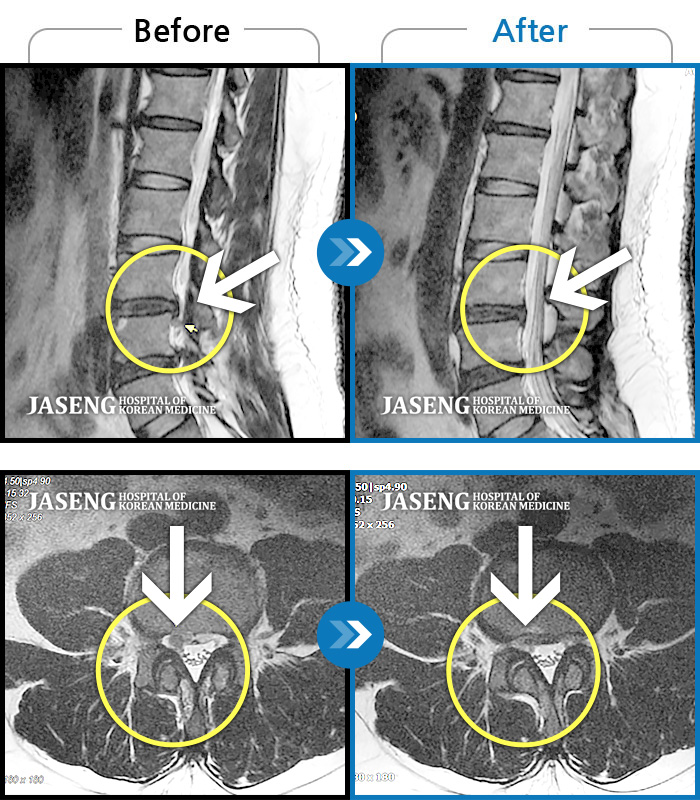

Before

After

환자에게 사전 동의를 받아 동일 조건에서 촬영되었습니다.

개인에 따라 치료 후 부작용이 발생할 수 있으니 의료진과 상담 후 치료를 진행하시기 바랍니다.

허리를 굽히거나 걸을때 양쪽다리 통증

좌측 하부요추부터 골반통증 및 양측 하지 방사통